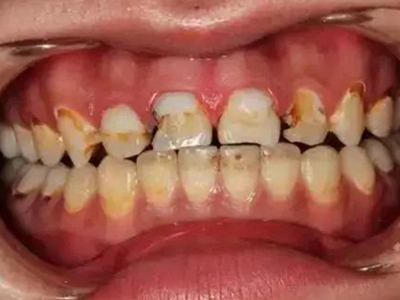

酸蚀症牙齿缺损不平整图

酸蚀症患者的牙齿会发生缺损,轻度时仅表现为牙齿尖端凹凸不平,有少量骨质缺失,缺损处有黄褐色至红褐色斑点,该病可能是长期接触外源性酸性物质而致病。

酸蚀症牙齿缺损严重有黑斑图

酸蚀症严重时会使牙齿出现大面积缺损,有三颗下牙损毁严重,露出不整齐的牙骨质边缘,几乎仅余留牙根。缺损处有黑斑,局部呈黄褐色,需积极就医进行牙齿修复。